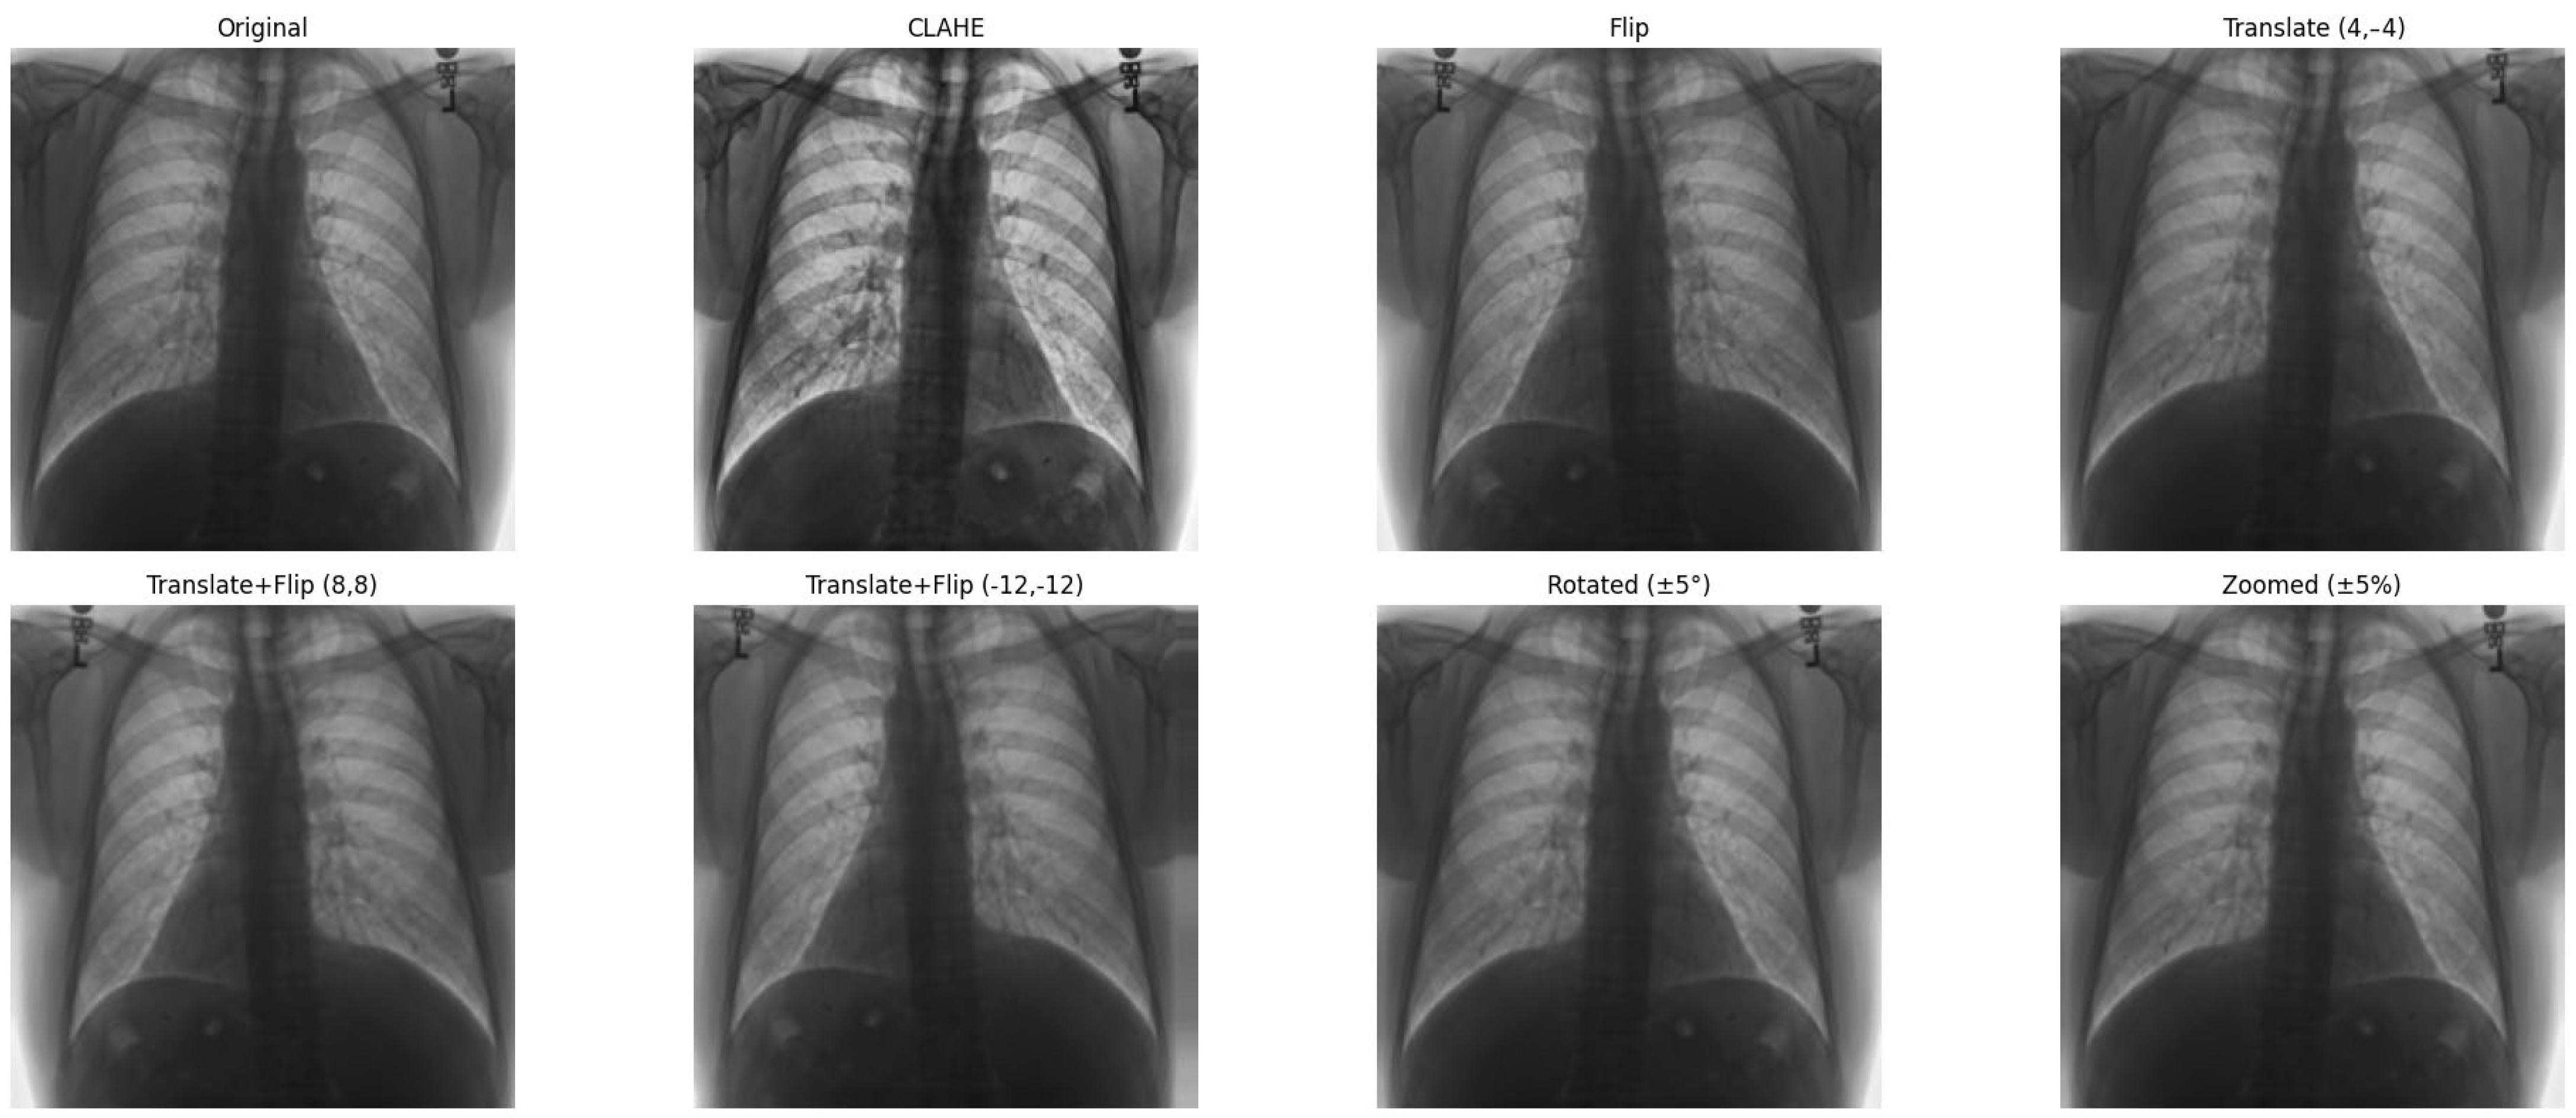

Figure 7 shows examples of images to which data augmentation techniques have been applied. Table 4 provides a detailed explanation of the types of data augmentation, their settings, and their clinical purposes.

Figure 7.

Data augmentation example.

Data augmentation was carefully designed to increase dataset variability while preserving the thoracic anatomical structures critical for cardiomegaly assessment.

Horizontal flipping was applied with a 50% probability, as frontal chest radiographs maintain diagnostic validity regardless of left–right symmetry in most cardiomegaly cases [29].

Rotation was constrained to a small range of ±5 degrees, as larger rotations could deform key structures such as the heart silhouette or mediastinum, which are essential for accurate diagnosis.

Zoom augmentation was applied within a narrow range of 95% to 105%, simulating realistic changes in radiographic magnification during image acquisition while avoiding the disproportionate enlargement of the heart or lungs.

Translation was limited to ≤5% of the image width or height (i.e., maximum shifts of approximately ±10 to 12 pixels) along the x- and y-axes to simulate minor variations in patient positioning without displacing core anatomical features.

Additionally, combinations of flipping and translation were used selectively to further enhance spatial diversity without compromising clinical interpretability [29].